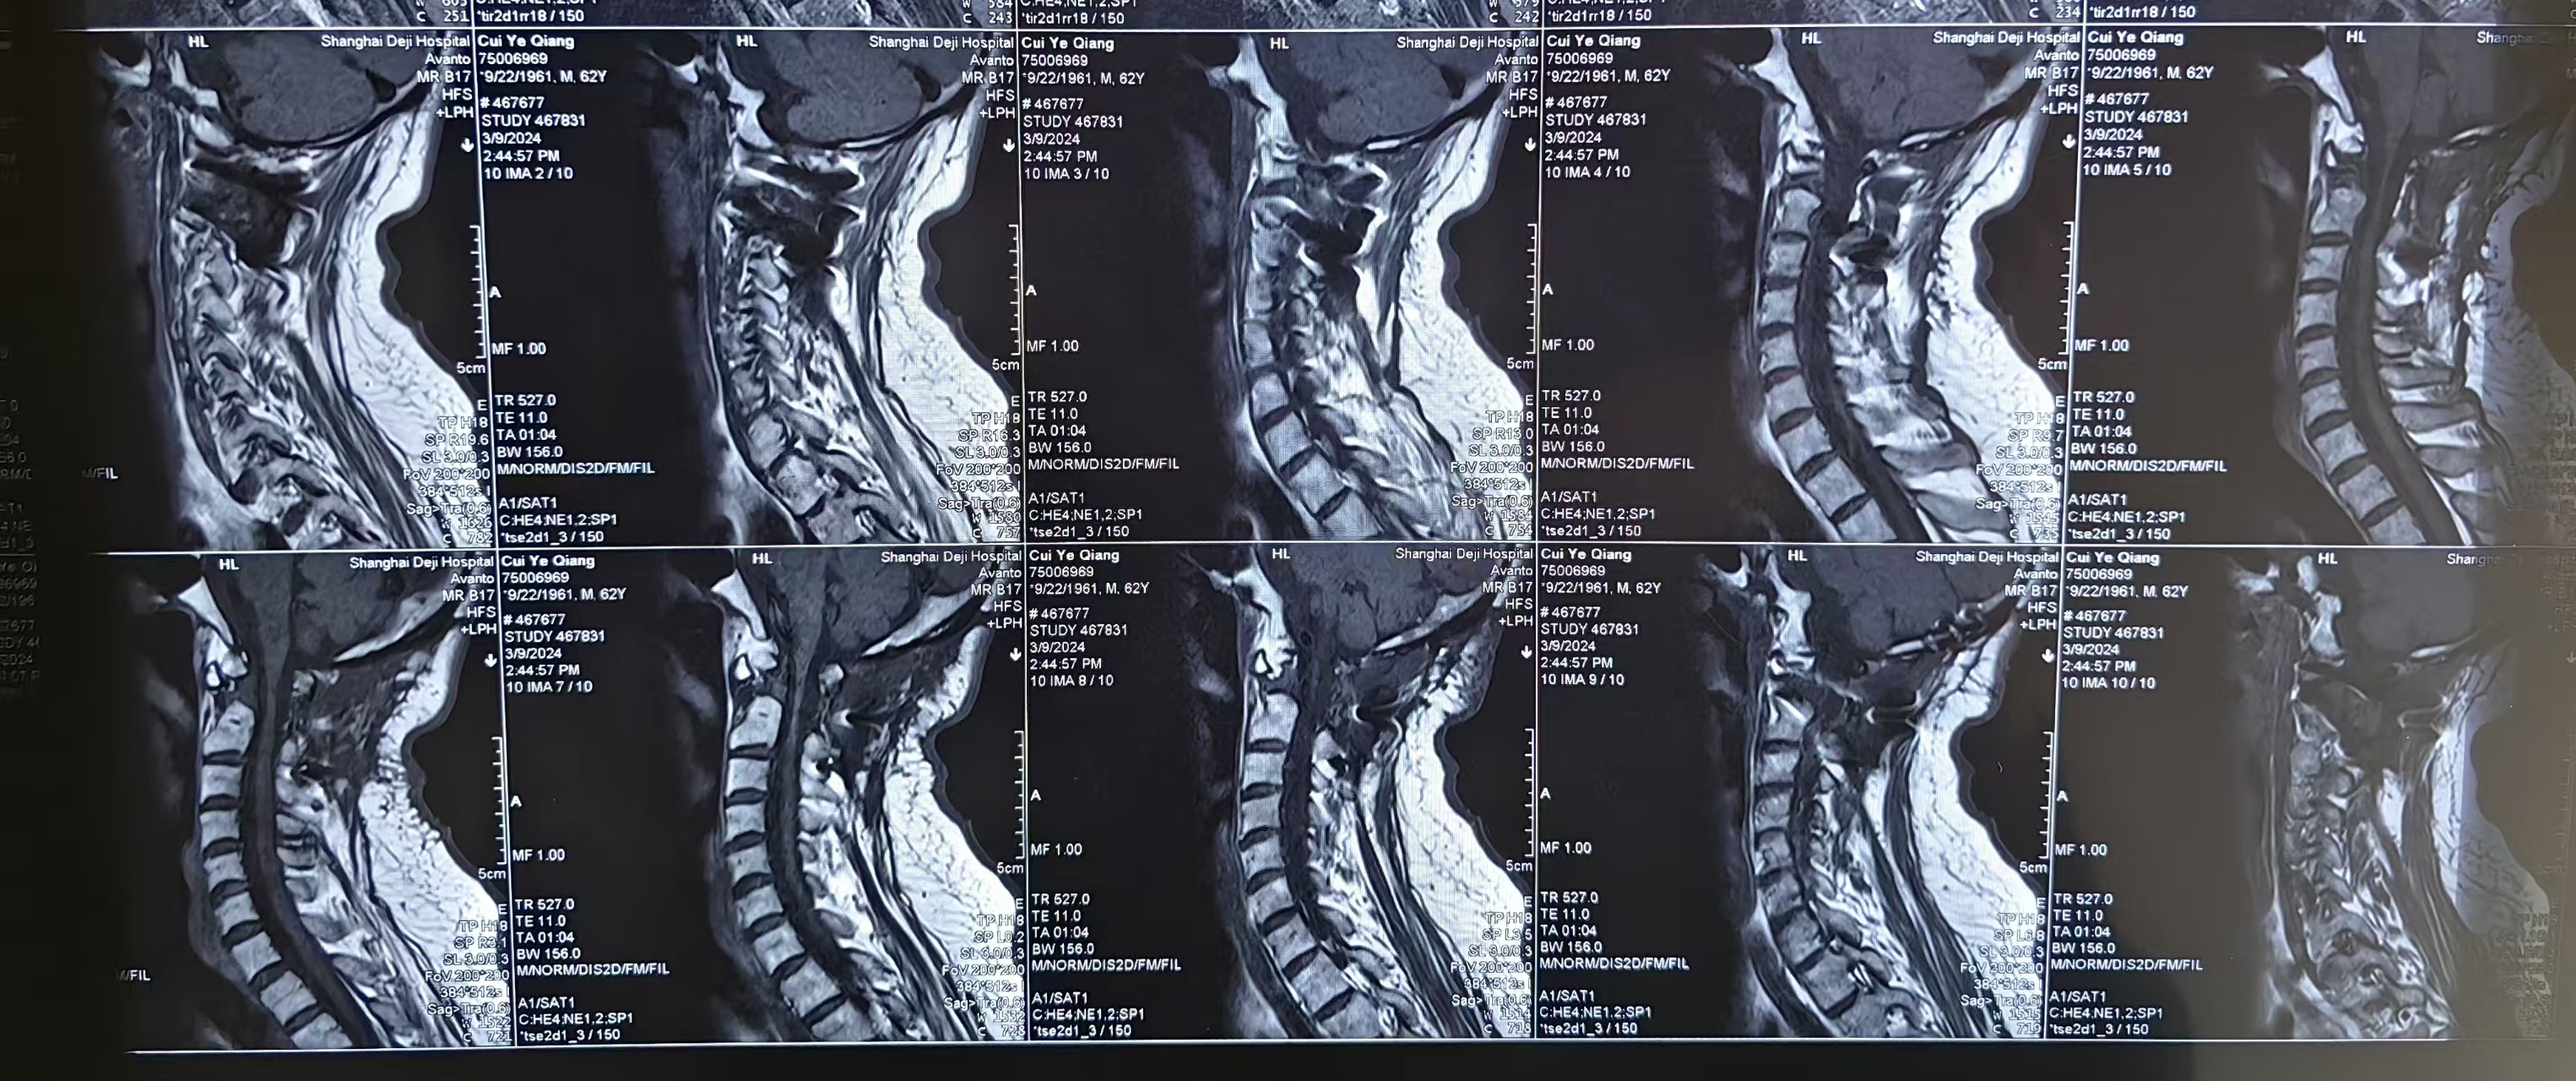

• 2024.03.09,复查,对位良好,但术前症状难以恢复。